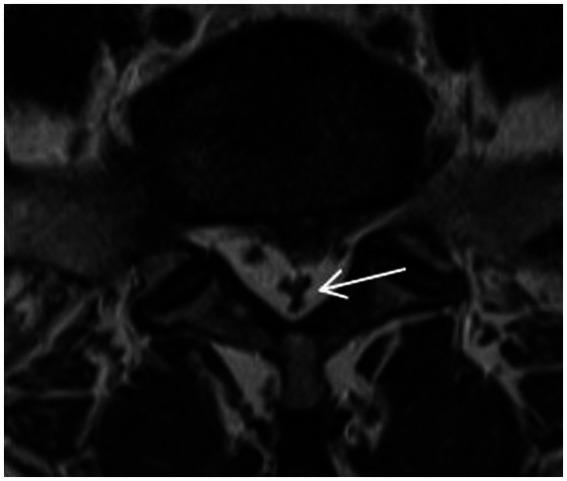

METHODS

878 patients diagnosed with LSS by clinical and MRI were divided into the redundant group (204 patients) and the nonredundant group (674 patients) according to the presence or absence of redundant nerve roots (RNRs). The anteroposterior diameter of the spinal canal (APDS) and the presence of multiple level stenosis, disc herniation, thickening of ligamentum flavum (LF) and increased epidural fat were assessed on MRI. Univariate and multivariate logistic regression analyses were performed to explore the predictors of LSS combined with RNRs.

RESULTS

Patients with LSS combined with RNRs had thicker epidural fat, smaller APDS and more combined multifaceted stenosis. Female patients and older LSS patients were more likely to develop RNRs; there was no difference between two groups in terms of disc herniation ( > 0. 05). Age, APDS, multiple level stenosis, and increased epidural fat were significantly correlated with the formation of LSS combined with RNRs ( < 0.05).

方法

878例经临床及MRI诊断为LSS的患者,根据是否存在神经根冗余(RNRs)分为冗余组(204例)和非冗余组(674例)。在MRI上评估椎管前后径(APDS)以及多节段狭窄、椎间盘突出、黄韧带(LF)增厚和硬膜外脂肪增多的情况。进行单因素和多因素逻辑回归分析,以探索LSS合并RNRs的预测因素。

结果

LSS合并RNRs的患者硬膜外脂肪更厚,APDS更小,合并多节段狭窄更多。女性患者和年龄较大的LSS患者更易出现RNRs;两组间椎间盘突出情况无差异(P>0.05)。年龄、APDS、多节段狭窄和硬膜外脂肪增多与LSS合并RNRs的形成显著相关(P<0.05)。